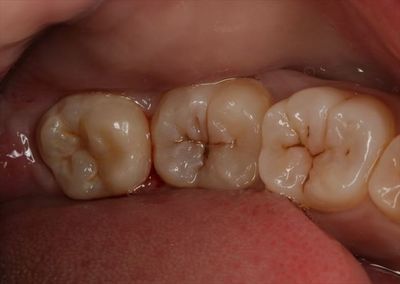

IMG_0396_R24.JPG

実際の左上親知らずです。(右端)

IMG_0397_R24.JPG

実際の左下親知らずです。(左端)